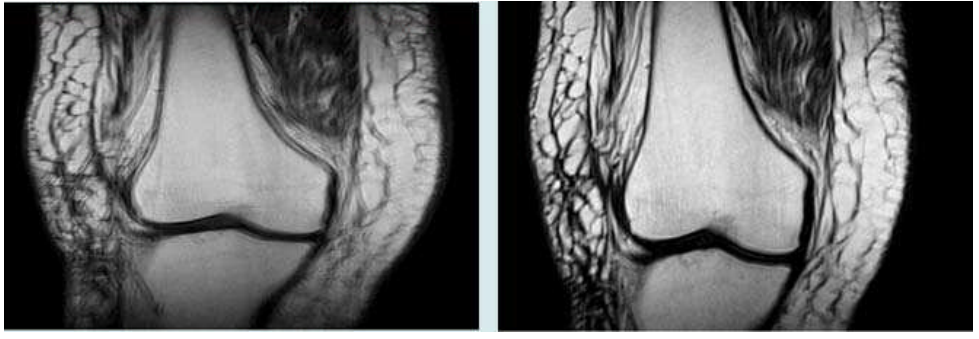

43.膝關節MRI檢查時發生左圖所示之假影,改善後影像如右圖。最可能的原因為 何?

(A)截斷假影(truncation artifact) (B)血流假影(flow artifact) (C) 反褶假影(aliasing artifact) (D) 移動假影(motion artifact)